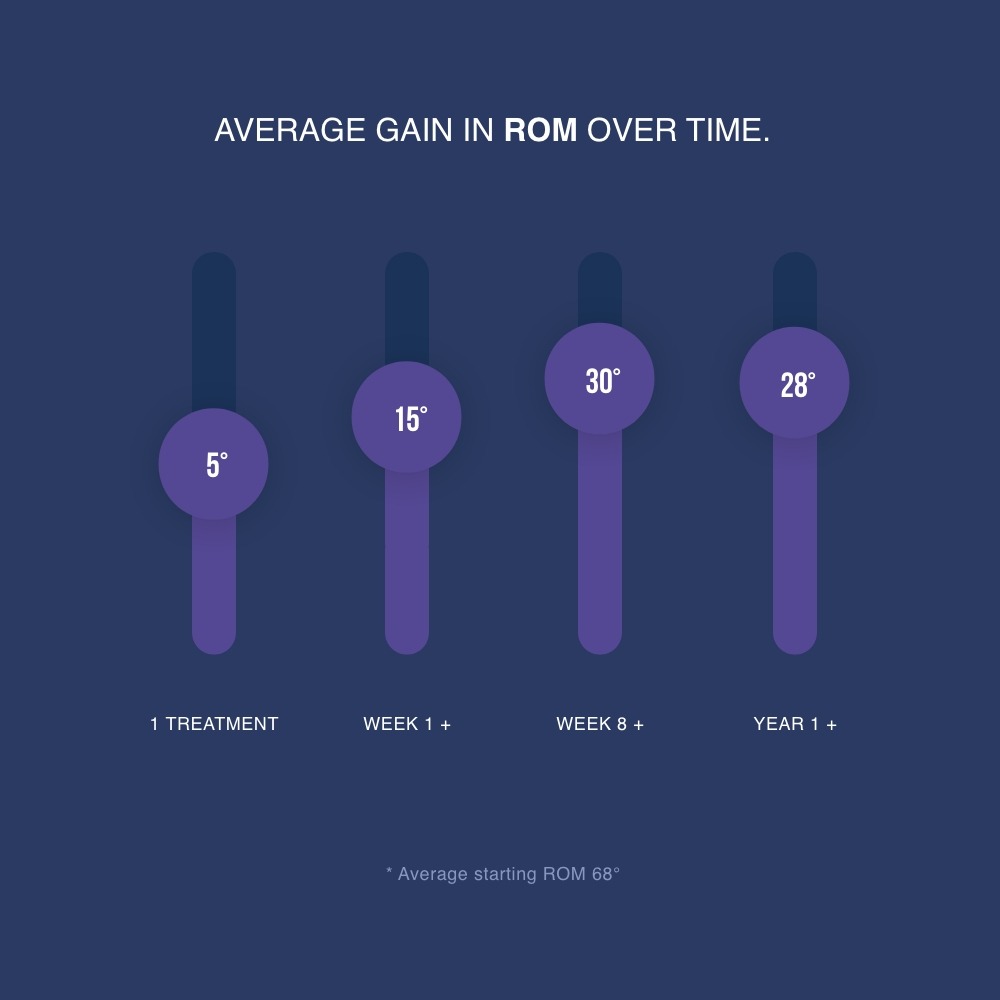

OUR PATIENTS RESULTS SO FAR…

The results include patients treated anywhere from a few weeks after surgery for as long as 8 years. It’s never too late.

The mean range of movement prior to the STAK was 72° (range 27 to 110 °) mean gain following STAK treatment (4-8 weeks) is 32° (range 12-60°).

In a clinical trial lasting 8 weeks, arthrofibrosis patients using the STAK gained on average 30 degrees range of movement compared to patients receiving standard physiotherapy who gained only 8 degrees.

“In a clinical trial patients using the STAK increased their ROM on average 30° compared to receiving standard physiotherapy gained only 8°. The STAK patients also reported greatly reduced knee pain.”

Significantly more effective than the current Usual Care. The STAK Tool improved knee joint flexion by 30.4° vs to 7.7° for Usual Care over an 8-week intervention and maintained after 12-months.